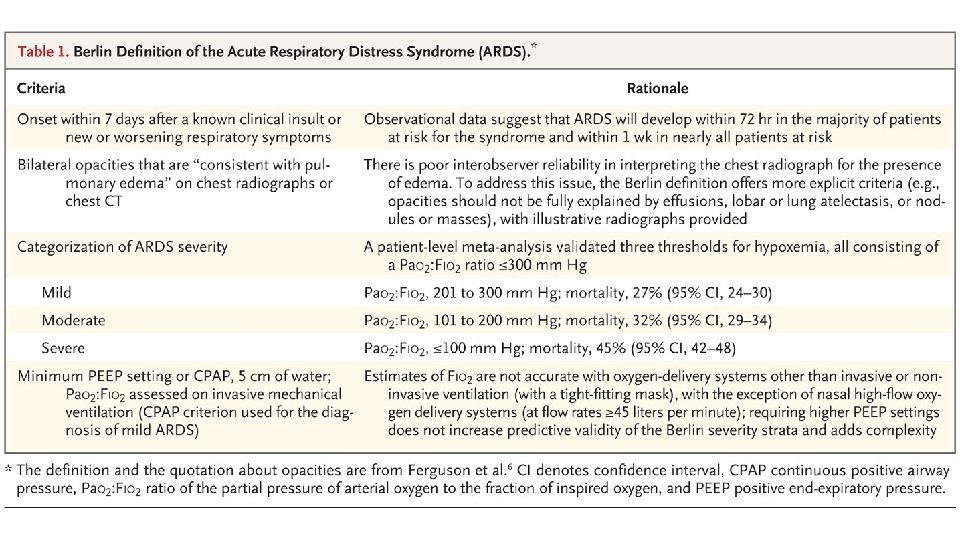

Acute Respiratory Distress Syndrome • Bernard GR, Artigas A, Brigham KL, et al. The American-European Consensus Conference of ARDS: definitions, mechanisms, relevant outcomes, and clinical trial coordination. American Journal of Respiratory and Critical Care Medicine. 1994; 149: 818 -824. • • • Acute Onset Bilateral Infiltrates on Chest x-ray Hypoxaemia Pulmonary Artery Occlusion Pressure <18 mm. Hg No validated diagnostic biomarkers are available

Pa. O 2/Fi. O 2

Acute Lung Injury <300 mm. Hg Pa. O 2/Fi. O 2 ratio Acute Respiratory Distress Syndrome <200 mm. Hg